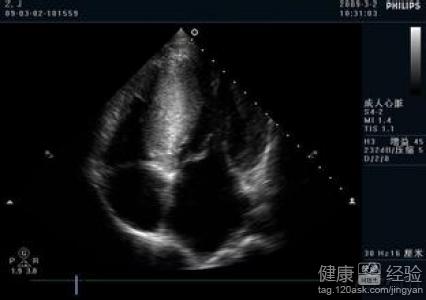

我今年已經有三十一歲了,我父親就患有過肥厚型非梗阻性心肌病,以前我上網查過這個病,知道會有一定的遺傳因素。但是因為這些年我一直也沒有發病,所以我還以為我沒有得過這個病。直到今年四月份的時候,我突然感覺到有了胸悶的情況,到醫院檢查後,發現竟然是患有了肥厚型非梗阻性心肌病而且還是遺傳性的疾病,那到底這個病可以治療好嗎?